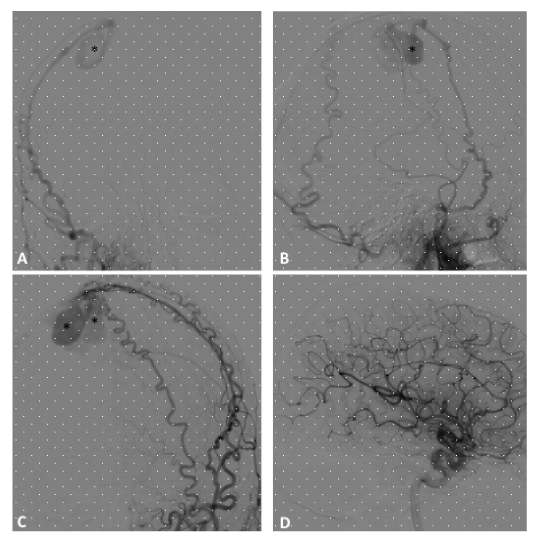

Figure 2 A. Post-embolization radiography, lateral view, showing the cast of Onyx occluding the middle meningeal artery and the occipital artery through an arterioarterial reflux. B. DSA of the common carotid artery, lateral view, showing complete occlusion of the fistula. C and D, DSA of the common carotid artery, lateral and anteroposterior view, showing the patency of the lateral sinus. The patient had resolution of his pulsatile tinnitus, persisting at a 3 years follow-up. s

Figure 3 A 43-year-old woman developed a left pulsatile tinnitus. A and B (left ECA injection, lateral projection) C and D (left ECA injection, AP projection) DSA showing a Borden and Cognard grade II IDAVF with multiple shunts between the occipital artery (white arrow), parietal branches of the middle meningeal artery (white arrowheads) and left transverse sinus (asterisk). There is retrograde flow into cortical veins (black arrows). Note the associated sigmoid sinus stenosis (black arrowhead), Just upstream to jugular bulb.

Figure 4 A (anteroposterior) and B (lateral), radiography showing the cast of Onyx obliterating the parietal branches of the middle meningeal artery with arterioarterial reflux into homolateral feeders, the cast extending to the arteriovenous junction and the proximal venous outflow. C Anteroposterior and D lateral projections DSA of the common carotid artery demonstrating a complete obliteration of the fistula.